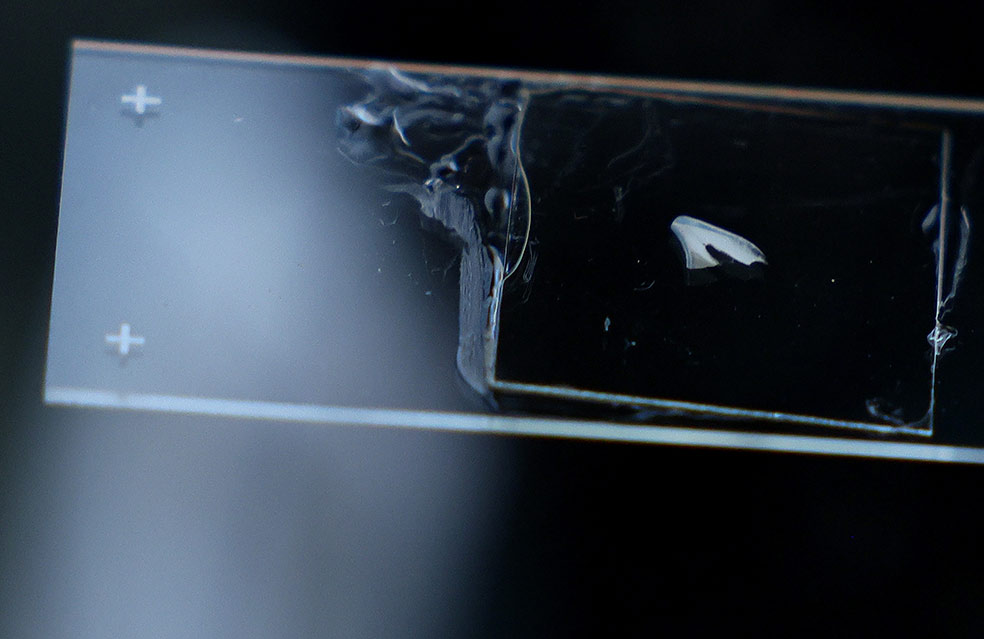

Si la violencia u otro trauma o dificultad (léase guerra o desastre natural) ha aparecido en la infancia, durante el desarrollo de la estructura cerebral, es fácil que los niños crezcan con problemas cognitivos o emocionales o una mayor propensión a padecer cáncer o enfermedades coronarias. Para la investigadora Erin Dunn resulta importante contar con un indicador objetivo que muestre problemas psiquiátricos padecidos en la infancia. Y lo ha encontrado en los dientes que decenas de voluntarios le envían. Son analizados por rayos X y tomografía axial antes de cortarlos en finas 'rebanadas' que permiten analizar los anillos de esmalte. Y buscar huellas de eventos traumáticos.